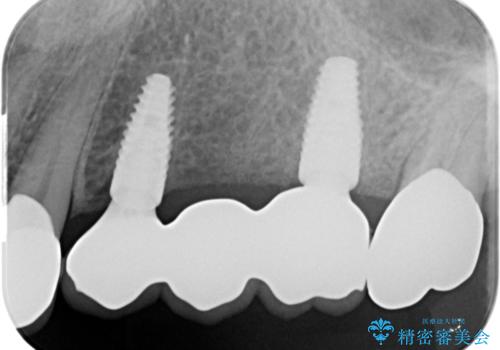

- 110万円(インプラント×2・チタンカスタムアバットメント×2・ジルコニアクラウン×3・仮歯×3)費用は治療当時の料金となります

インプラント2本で3本分の咬合機能を回復することができました。(インプラントブリッジ治療)